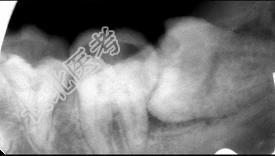

- 多项选择题关于阻生牙阻力来源正确的是 ( )

A、阻力来源于邻牙

B、阻力来源于骨组织

C、阻力来源于牙龈

D、阻力来源于咀嚼肌

E、阻力来源于对

牙